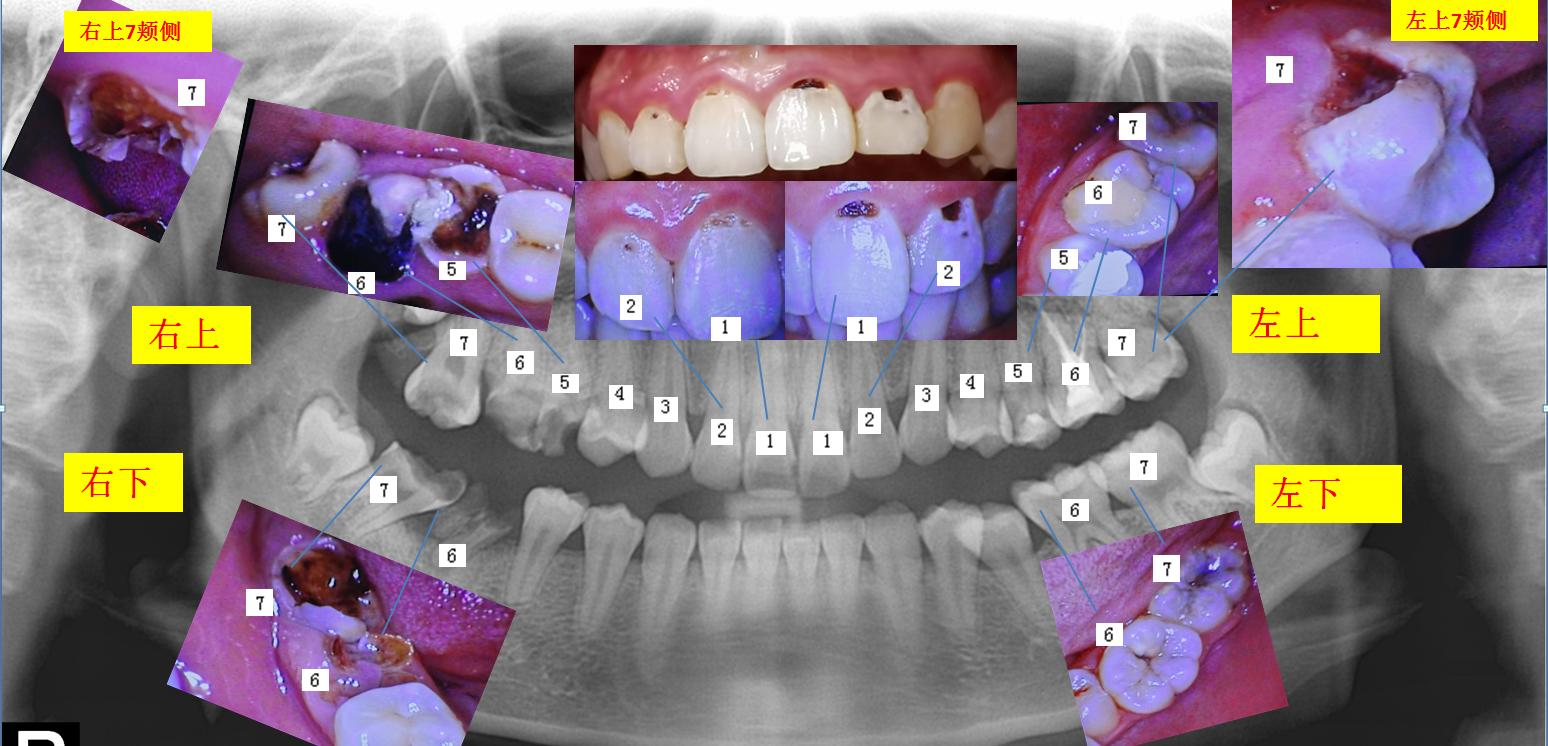

(上图是拔除了龋坏严重的第一磨牙,通知正畸处理,把多余的智齿利用了起来。)